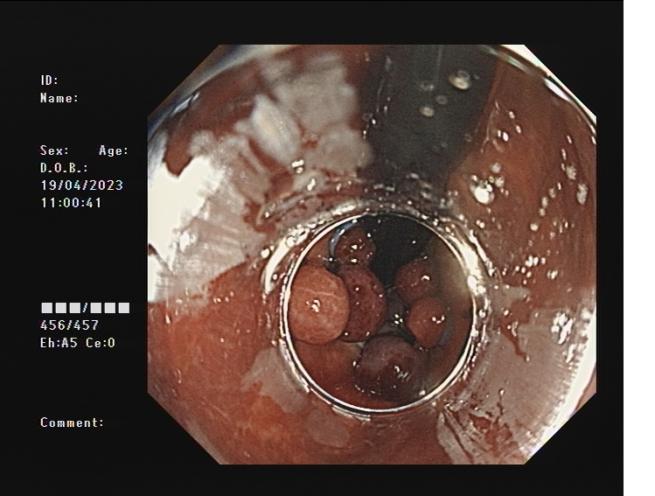

內痔                    內鏡下內痔硬化治療

內鏡下內痔硬化術:治療I-Ⅲ度內痔伴有內痔相關癥狀;I~Ⅲ級內痔飲食及藥物治療無效;內痔手術后復發,肛門反復手術后不能再次手術;恐懼外科手術,不愿意接受手術治療;高齡、高血壓、糖尿病和嚴重的系統性疾病,不能耐受外科手術等。